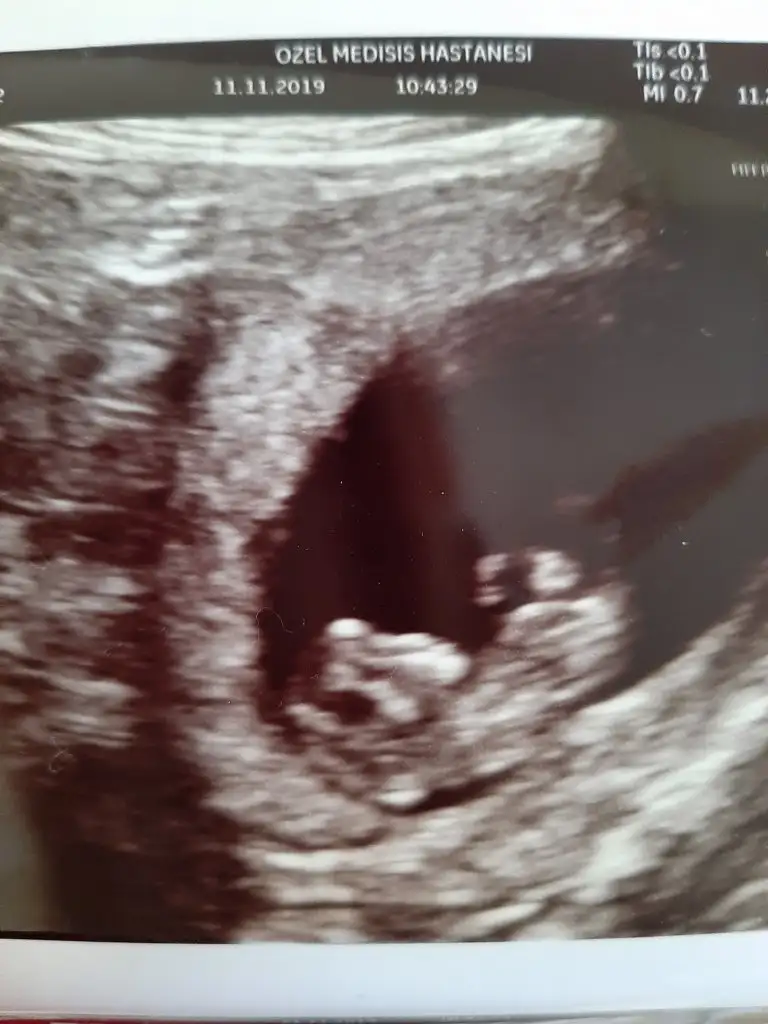

Arkadaşlar mesajim gerilerde kaldi yardimci olabilecek olan var mi acaba goruntu net olmayinca icime bir kurt duştuKizlar bugun doktora gittim pelvik bolgemde bası hissediyordum. Hersey nornal dedi ama goruntu net degildi. Eli bacakalri sutekli hareket ediyordu biraz hareketli dedi doktor. Ama goruntu net olmadigi icin ikili tarama icin alttan bakariz dedi. Bu durumda olan oldu mu kizlar hic.

Goruntusu boyle bacilarim depresyonlara giriyorum ben galiba bu vesveselerim beni bitirecekArkadaşlar mesajim gerilerde kaldi yardimci olabilecek olan var mi acaba goruntu net olmayinca icime bir kurt duştu

Ultrasonun kalitesine göre değişir benim devlette belli bile olmuyor özelde çok net bence sizinki de net ama hareketliyse bebek daha net görüntü için vajinal bakmak istemiştir doktorunuzGoruntusu boyle bacilarim depresyonlara giriyorum ben galiba bu vesveselerim beni bitirecek